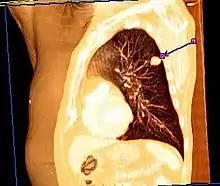

Représentation en coupe tridimensionnelle par tomodensitométrie d'un poumon présentant une tumeur.

Scanner montrant une tumeur cancéreuse dans le lobe supérieur du poumon gauche.